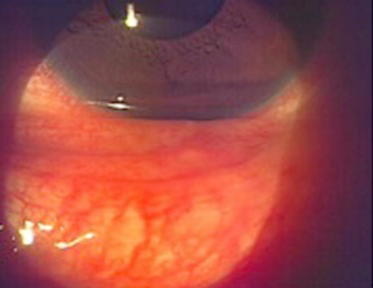

瞼の裏側にぶつぶつや充血・流涙が強く見られます。感染して7~12日位で発病します。